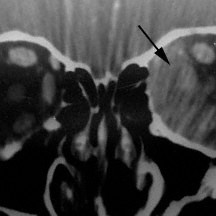

Optic nerve sheath meningioma

Optic nerve sheath meningioma (arrow head)- Computed radiographic tomography (CT).